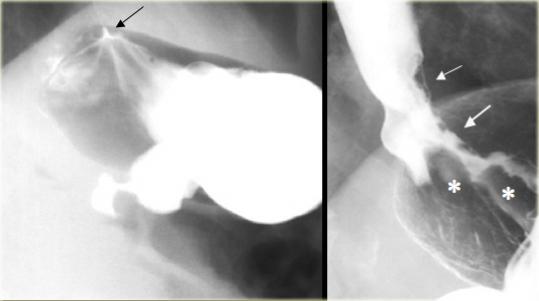

Nối thực quản – dạ dày bình thường (trái), Ung thư biểu mô tuyến vùng đáy vị xâm lấn thực quản (phải)

Tại vùng nối thực quản – dạ dày, các nếp niêm mạc trơn nhẵn và đều đặn ở đáy vị hội tụ về phần thực quản xa nhất (mũi tên).

Hình ảnh bên cạnh cho thấy vùng nối thực quản – dạ dày bất thường: Baryt bao phủ các nếp niêm mạc dày và không đều (dấu hoa thị).

Ung thư biểu mô tuyến vùng đáy vị xâm lấn thực quản (mũi tên)